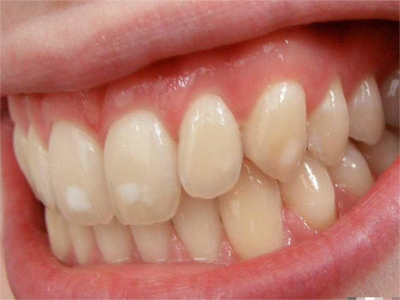

牙釉质发育不全牙齿表面有白色斑块图

牙釉质发育不全患者病情较轻时,只出现色泽、透明度改变,牙齿表面出现不规则的白色斑块,透光度降低,但牙齿形态较完整,无明显缺损。